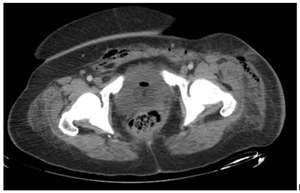

A 43-year-old female with morbid obesity (BMI 42), a history of type 2 diabetes diagnosed 12 years ago without treatment or follow-up, one cesarean section in 2011 and bilateral tubal occlusion in 2018. Who begins with sudden pain in the left inguinal region associated with swelling. She received analgesic treatment without improvement and decided to attend the hospital where is diagnosed with septic shock secondary to soft tissue infection. The results of the blood cytometry were leukocytes 21 000/mm, neutrophils 89%, lymphocytes 6%, hemoglobin 9 mg/dL, hematocrit 28%, and platelets 21 000/mm. Surgical drainage was done and a vulvar abscess was found, dissecting from the mount pubis to the ischiopubic fossa with necrotic tissue and fetid purulent material. During her postoperative period, she continued with purulent secretion outflow; a tomographic study showed the presence of fluid between the subcutaneous cell tissue and the muscular abdominal wall associated with subcutaneous emphysema (Figure 1 & 2). A reintervention was decided for surgical debridement and lavage, among the findings were: labile tissue with fetid necrotic edges, purulent secretion from the left genital area, inguinal region, abdominal subcutaneous cell tissue to the external oblique aponeurosis (Figure 3). In the postoperative period, multiple surgical lavages and debridements were carried out, followed by a VAC system. Nutritional parameters were below the acceptable level, parenteral nutrition was started and enteral nutrition with arginine boluses. A curve of nutritional parameters (albumin, prealbumin, ferritin and transferrin) was made prior to the establishment of the VAC system (Figure 4 & Table 1).

Figure 1 CT scan prior to second intervention that shows subcutaneous emphysema and what it seems and abscess formation.